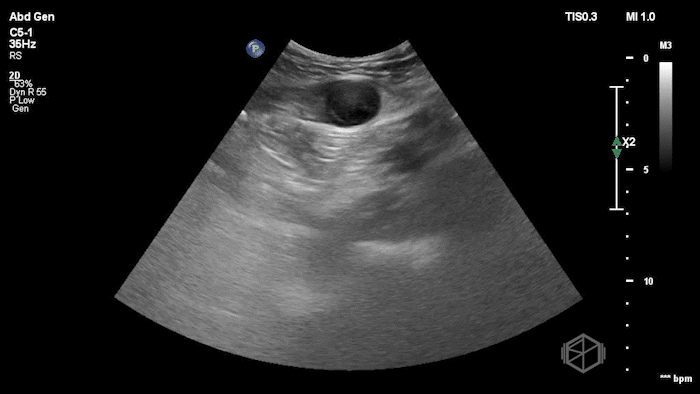

Given the patient’s focal abdominal wall tenderness, a POCUS exam of the left lower quadrant at the point of maximal pain was performed.

She obtained the following images:

The POCUS shows an hypoechoic circular mass within the rectus muscle. There is no active color doppler flow suggesting likely no active bleeding.

Diagnosis: Rectus sheath hematoma (RSH)